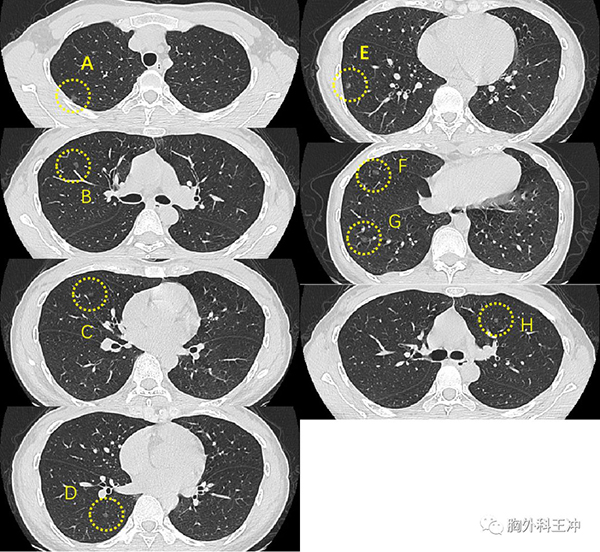

基本情况 男性,44岁,2019年6月体检发现双肺多发磨玻璃结节,较大者位于右肺上叶。

手术方式 VATS右肺上叶楔形切除、淋巴结采样术

病理结果 微浸润腺癌,浸润灶直径2mm

基因检测 exon2 MAP2K1

手术理由 1、形态典型,早期肺癌可能大;

2、右肺上叶病灶A最大,位置靠近肺尖,好切,肺损伤小;

3、左肺病灶较小,可先观察;

4、患者有手术意愿,希望明确诊断;

故进行右肺上叶楔形切除。

下一步治疗 有基因突变但无对应药物,术后定期复查

基本情况 女性,33岁,体检发现双肺多发磨玻璃结节3年,定期复查未见变化。

手术方式 VATS右肺上叶楔形切除、下叶楔形切除、淋巴结采样术

病理结果 病灶A:原位腺癌

病灶E:微浸润腺癌,浸润成分乳头型、腺泡型,浸润深度2mm

病灶F:原位腺癌

基因检测 未做

2、右肺为主,部分结节靠近胸膜,可切除明确诊断,损伤小;

3、患者观察时间较长有手术意愿,希望明确诊断;

故进行右肺上叶楔形、下叶楔形切除。

下一步治疗 术后定期复查